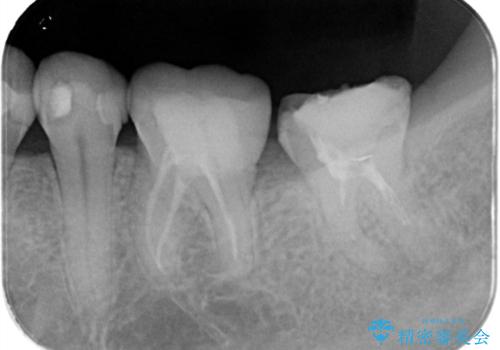

【根管治療】他院でインプラントの提案があった。奥歯が痛い。

- 左下の奥歯の治療の継続を主訴に来院されました。

1週間ほど前に、自発痛の既往があり他院で応急処置を行ってもらったとのことです。

そこでは、抜歯してインプラントの治療を提案されたとのことです。

レントゲンや口腔内所見にて以下のような説明ののち、患者様が保存を希望されたため、当院では根管治療~オールセラミッククラウンにて修復処置を行いました。痛みも消えて、経過良好です。

根尖部に透過像を認め、①何もしないと今後の経過として痛みが増悪することや、腫脹を伴うことがある。

病気の原因は細菌であるため、細菌数を減らすための処置として一般的に②根管治療という選択肢がある。再根管治療の場合は病気が治るのは7割ぐらいであり、それでも治らない場合は意図的再植術を行い9割近くまで成功率を高めることができる。ただし、今回のケースでは根尖が湾曲しているため意図的再植時の破折リスクが高いため適応は難しい。また、根尖の病変が治ったとしても、歯周病、カリエス、脱離や破折リスクがあり治療後抜歯になる可能性もある。治らない可能性や治療したとしても抜歯になる可能性があることを考慮し、③抜歯の選択肢をとる場合もある。